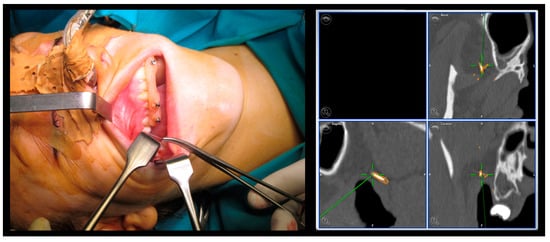

| Case 1 Foreign body | 1.00 mm | |||

| Case 2 Impacted teeth in Pfeiffer Syndrome | 0.5 mm | 0.3 mm | 0.6 mm | |

| Case 3 Impacted teeth in Apert Syndrome | 0.3 mm | 0.5 mm | 0.4 mm | 0.5 mm |

| Case 4 Impacted teeth | 0.3 mm | 0.2 mm |